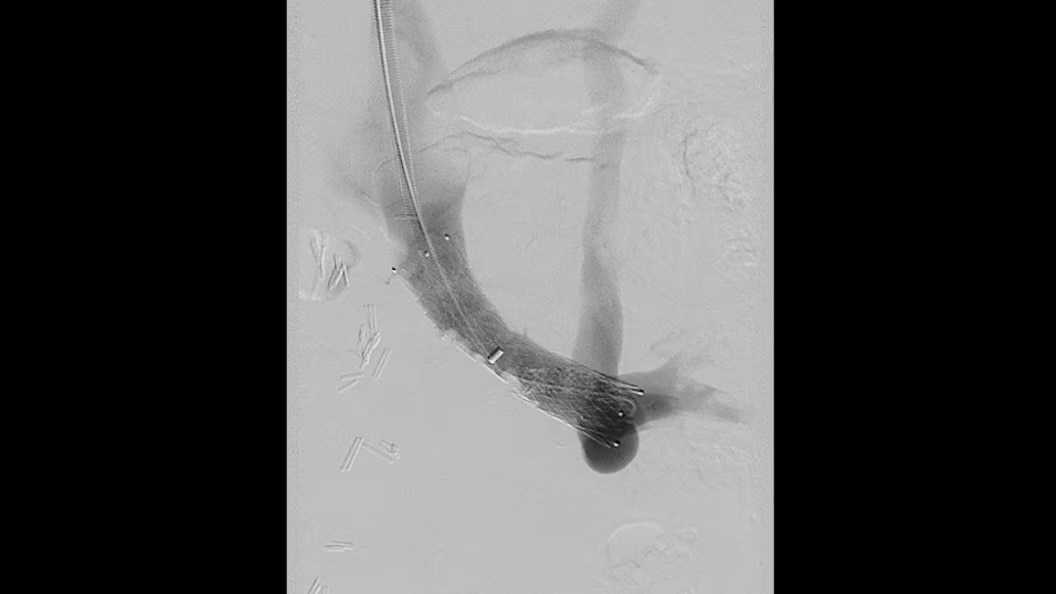

Embo ASSIST AI

Embo ASSIST1 with Virtual Injection, is a 3D Visualization software solution designed to help clinicians simulate injections dynamically and thus perform embolization procedures with confidence.